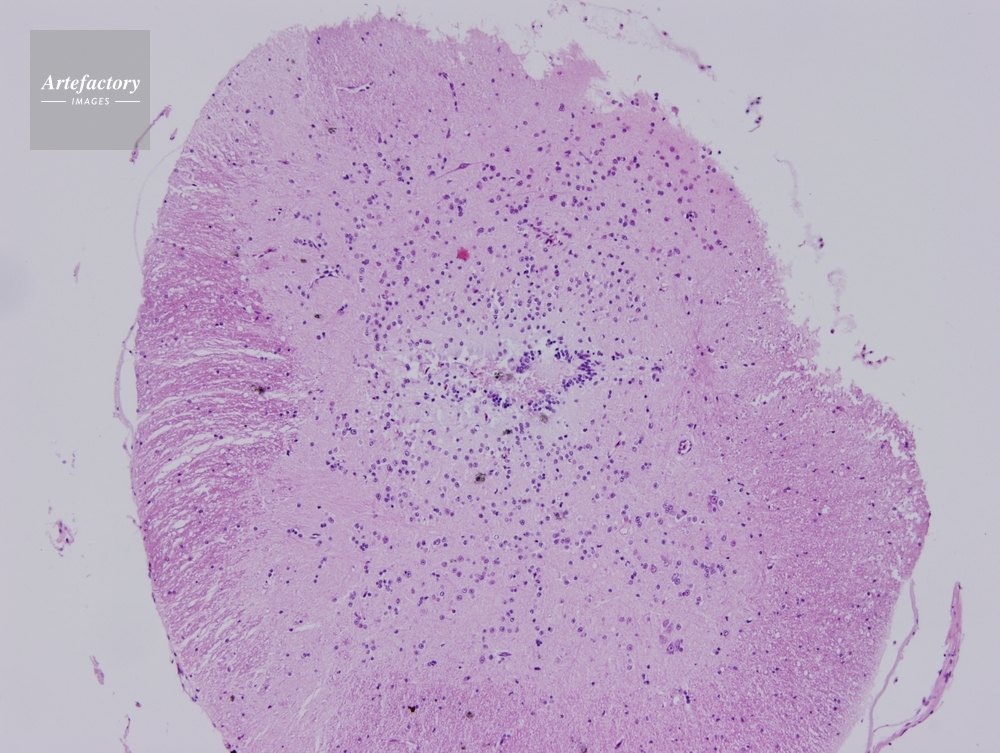

| 作品タイトル | ウシガエル 脊髄 | モデルリリース | なし | |

| 作家 | OLYMPUS CORPORATION Technolab | プロパティリリース | なし | |